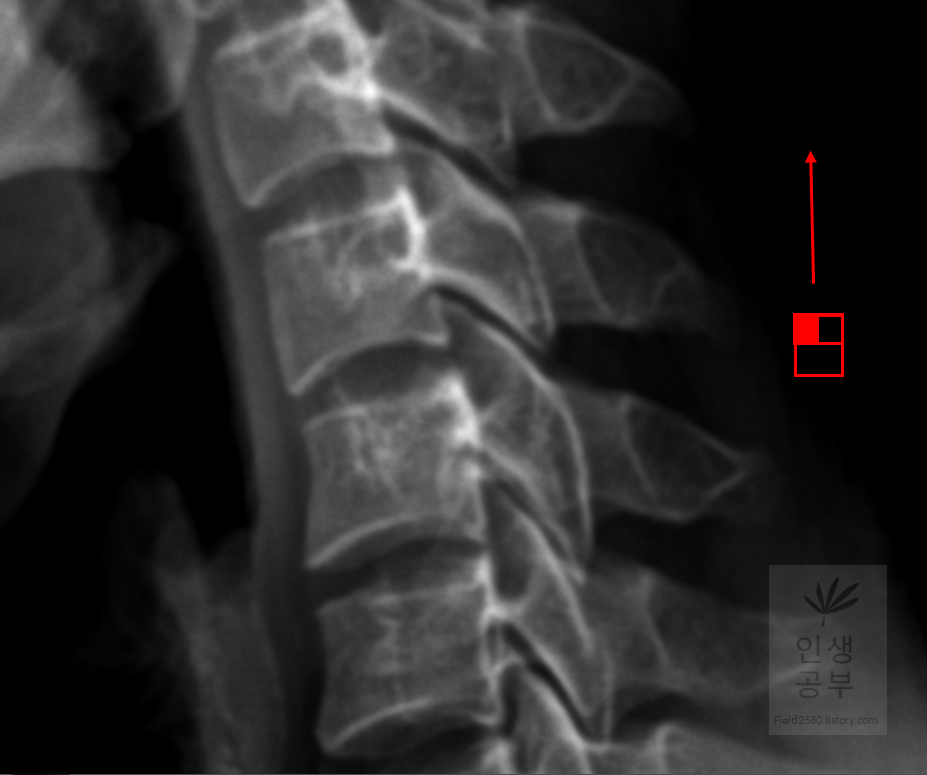

목의 정렬을 알아보기 위해서 목뼈의 선들을 연결해서 그어보는 방법에 대해서 알아보겠습니다. 도구 상자에서 빨간색네모상자 안에 있는 물결무늬 모양의 버튼을 눌러줍니다.

목뼈 추체 제일 앞쪽에 있는 선을 따라서 그어줍니다.

목뼈 추체 뒷면을 따라서 선을 그어줍니다.

Spinolaminal line을 따라서 선을 그어줍니다.

극돌기(Spinous process) 끝을 따라 선을 그어줍니다. 각각의 라인의 곡선의 커브가 자연스럽게 연결되었는지 확인해 줍니다. 이처럼 연결된 선을 이용해서 각각의 뼈의 정렬을 선을 그어서 알아보고 싶으면 곡선으로 그려진 버튼을 이용해서 확인할 수 있습니다.